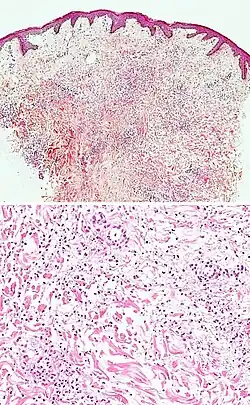

| Kaposi’s sarcoma in patch stage | The patch stage typically shows irregular proliferation of jagged vascular channels in the dermis below an integral epidermis. The so-called promontory sign is sometimes found in patch stage lesions and denotes vascular spaces surrounding pre-existing blood (see image).[23]

vessels |